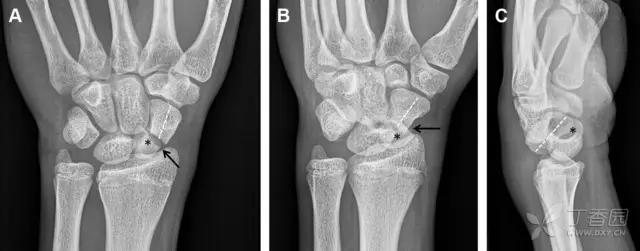

36 腕关节不稳定与脆弱区

月骨周围脱位和月骨周围骨折脱位常发生于摔倒后手掌撑地,由过伸、轴向*力暴**所致。所谓的「脆弱区」包括桡骨茎突、大多角骨、舟状骨、头状骨近端、钩状骨近端、三角骨的月骨缘、尺骨茎突。

图 7 经舟状骨骨折月骨周围脱位(腕关节前后位、斜位、侧位)。(A,B)前后位、斜位示月骨腰部骨折(黑箭头),第 1、2 腕弧中断,舟状骨近极(*)仍在原位,而远极(虚线)背侧脱位